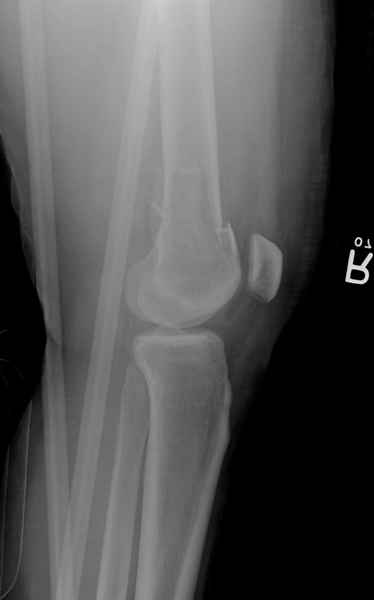

Привет из Нижнего Новгорода! К нам поступил пациент 25 лет с закрытыми переломами обеих бедренных костей, прошел месяц после травмы. Слева - внутрисуставной перелом, поэтому выбор здесь очевиден, открытая репозиция, стабильная фиксация, скорее всего LCP DF, а справа - мнения учёных, как говорится, разошлись. Лично я, как лечащий врач, за закрытый интрамедуллярный остеосинтез DFN. Со мной согласна половина коллектива, другая - за интрамедуллярный остеосинтез (DFN,UFN) но с открытой реопозицией, поскольку при закрытой методике все осколки останутся где-то сбоку, получится дефект и вдруг не срастется!Философский вопрос: что лучше - красивая рентгенограмма или сохранение кровоснабжения? Очень важно мнение коллег! Смирнов Алексей

Мы бы не стали открывать, такие переломы срастаются, хотя бы и с краевым дефектом. То есть если удалять стержень потом, то сильно попозже обычного. В приложении пример. Сразу после операции и через 11 мес. Понятное дело, пациент к тому времени давно и не хромал, и функция колена была полная.